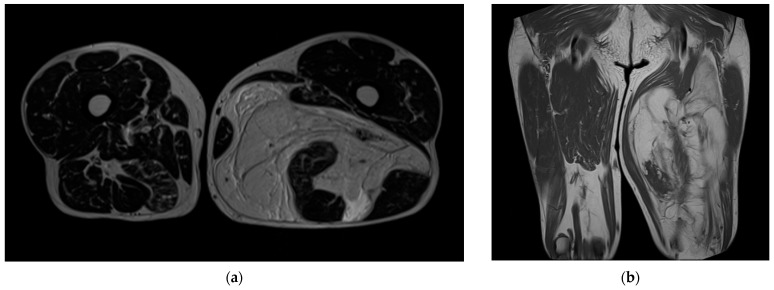

Background and Clinical Significance: Myxoid liposarcoma (MLS) is a malignant soft tissue tumor that often presents as a painless, slow-growing mass and is known for its atypical extrapulmonary metastatic pattern. Although sciatic nerve involvement is rare, when present, it usually causes neurologic symptoms. In this case, a large MLS silently expanded and completely encased the sciatic nerve without causing deficits, highlighting the importance of early imaging, multidisciplinary planning, and individualized surgical strategy in managing complex soft tissue sarcomas. Case Presentation: This case report describes a 67-year-old male with a 30 cm encapsulated myxoid liposarcoma of the posterior left thigh. The tumor had grown insidiously over one year and completely encased the sciatic nerve without causing pain, paresthesia, or motor impairment. Selective embolization was performed preoperatively to minimize blood loss. A posteromedial surgical approach allowed for en bloc resection with negative margins and preservation of sciatic nerve integrity. Histopathology confirmed a myxoid liposarcoma composed primarily of spindle-shaped tumor cells. The patient experienced no postoperative complications or neurologic deficits. At the two-year follow-up, he remains disease-free with full functional recovery. Conclusions: This case illustrates the potential for large, asymptomatic myxoid liposarcomas to encase critical neurovascular structures without infiltration. Preoperative embolization as part of a multidisciplinary plan was key to achieving safe resection and excellent functional outcomes.